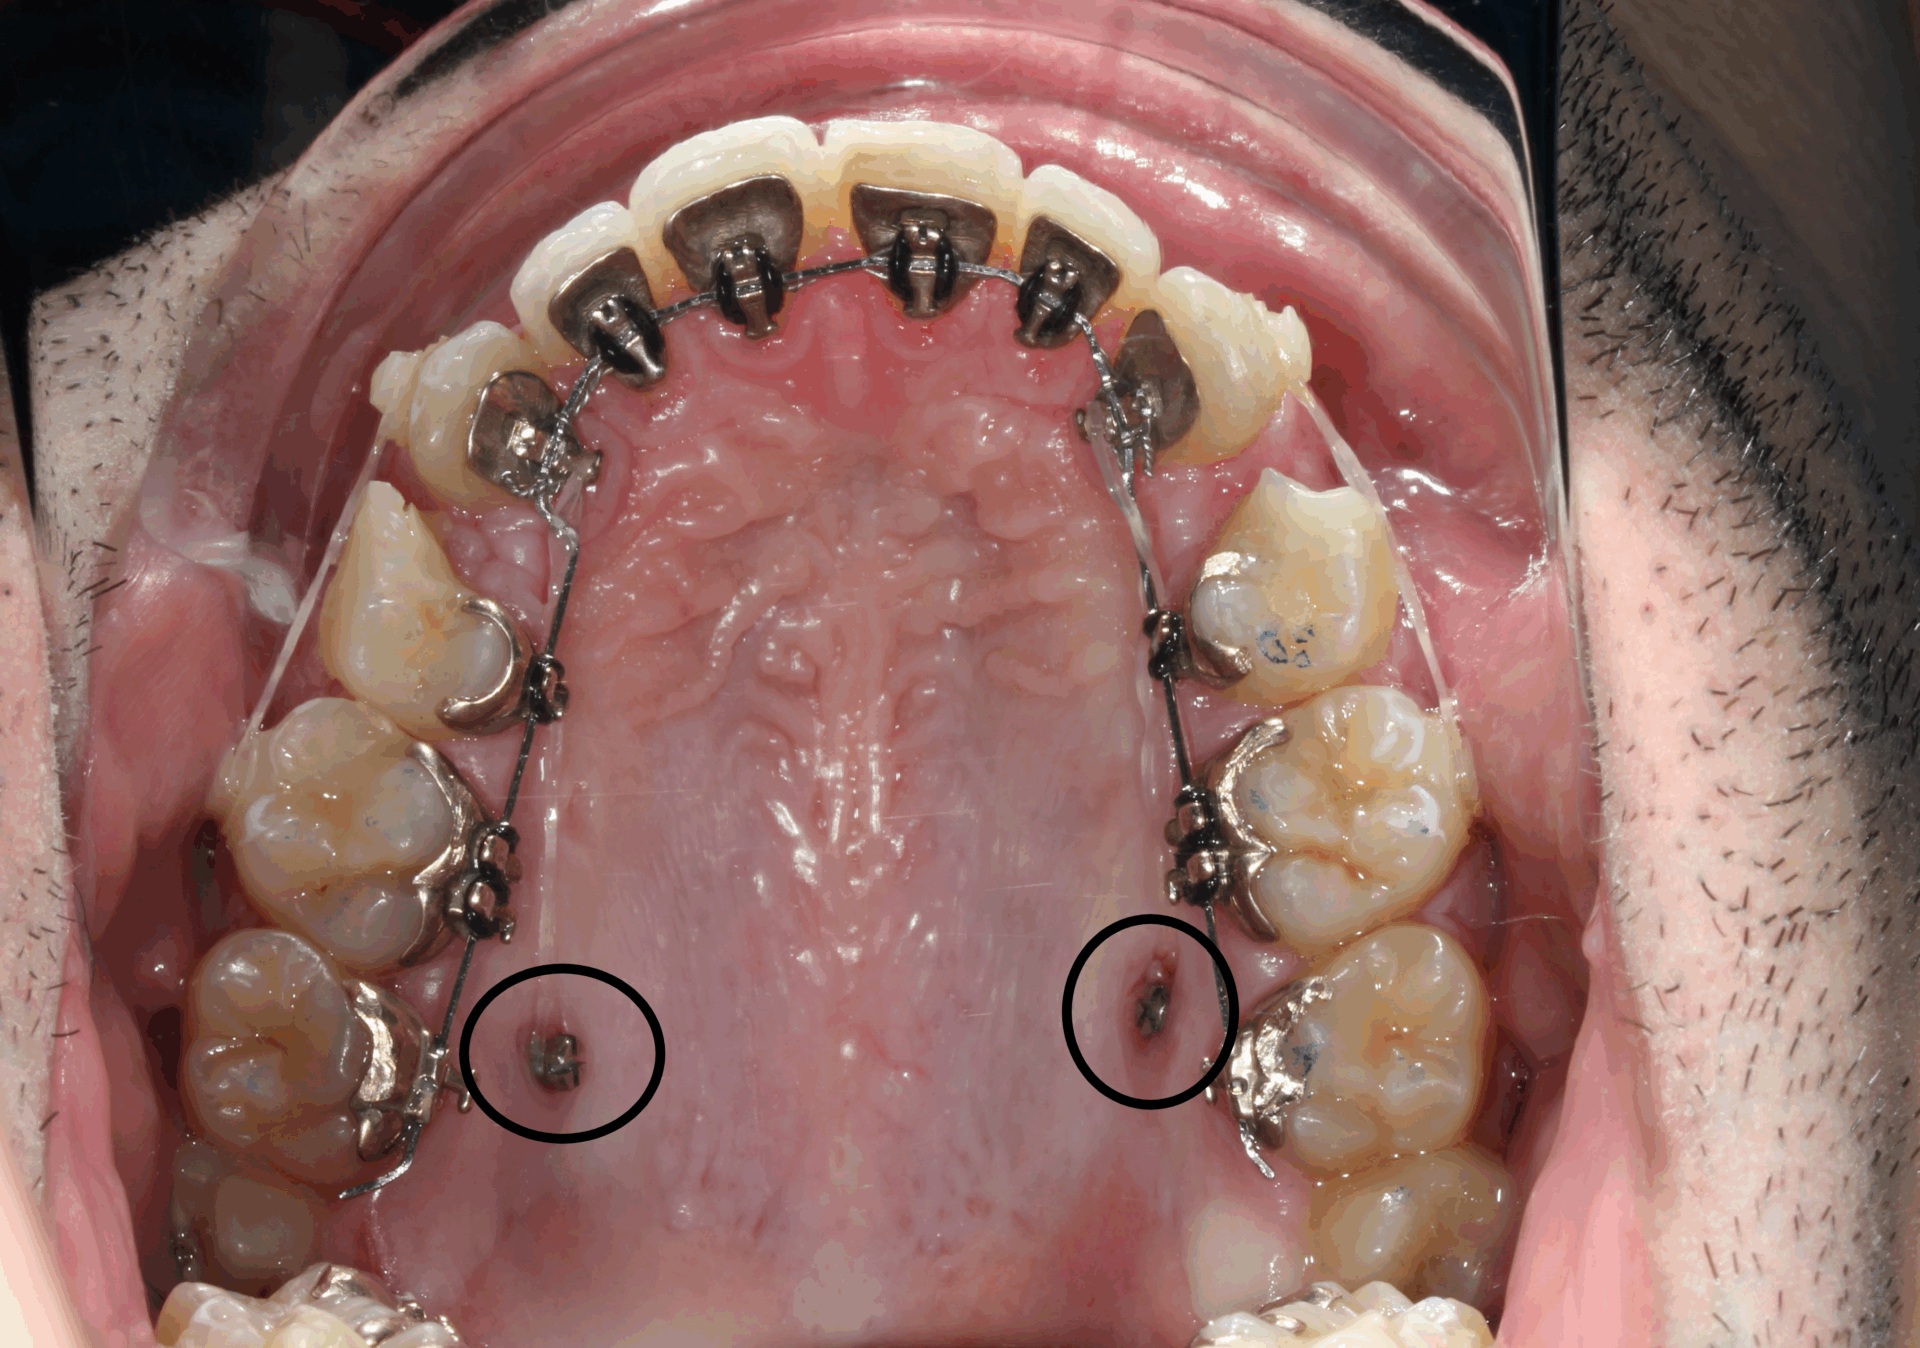

ORTODONCIA LINGUAL CON MICROTORNILLOS.

Ortodoncia lingual y microtornillos para alinear y nivelar arcadas.